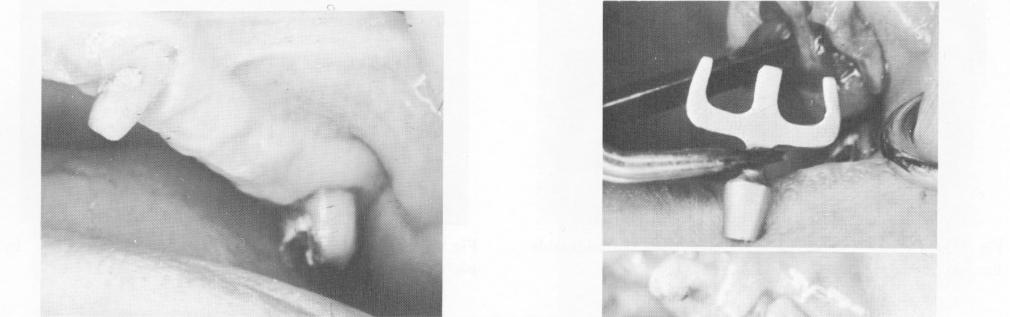

Fig. 11-68. The edentulous span between cuspid and second molar.

Only four of this patient's teeth remained: two maxillary cuspids and two molars. For additional support of a full arch restoration, a blade was diagnosed to be placed between the left cuspid and second molar (Fig. 11-68). The tissue was incised and

Fig. 11-69. The implant being seated in its site. (From Linkow, L. I.: The blade vent, a new dimension in endosseous implantology, Dent. Concepts 11:3-18, 1968.)

1 Edentulous span between maxillary cuspid and second molar

2 Blade seated in edentulous span between upper cuspid & second molar